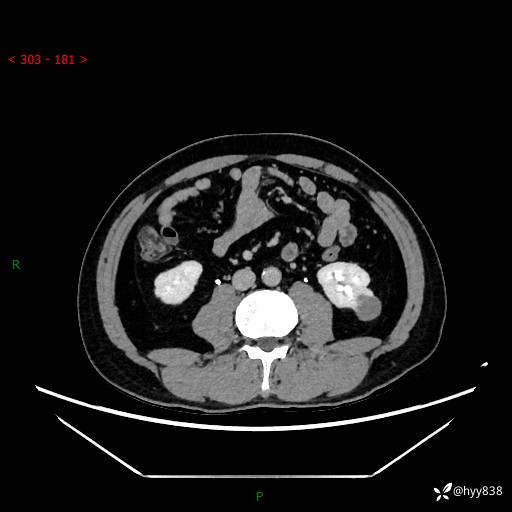

中年男性,左侧腰背部间断性胀痛不适。第一眼“乳头或囊肿”,有无意外---(有结果)

【患者信息】:41岁/男

【主诉】:左侧腰背部间断性胀痛不适1周

【现病史及既往史】:患者1周前无明显诱因出现左侧腰部疼痛,呈间断性胀痛,休息后可缓解,无放射痛,偶可见肉眼血尿,无血块,无尿频尿急尿痛,无夜尿增多,无畏寒发热、咳嗽咳痰等症状。于我院查双肾CT示:左肾占位性病变,左肾下极囊性病变,左肾轻度积水,胆囊多发结石。今为求进一步诊治来我院,门诊以“左肾占位性病变”收治入院。 起病以来,患者精神佳,饮食、睡眠良好,大便正常,小便如上诉,体力体重无明显变化。

【检查】:肾脏CT平扫+增强